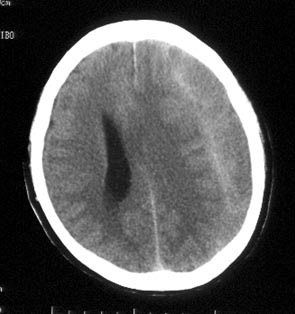

病史:男性,56岁,自觉右侧肢体肌力下降,伴麻木不适半月,逐渐加重。一个月前曾有头部轻微碰伤史,但具体经过不能回忆。

ct平扫:左额及颞顶叶见新月形略高密度血肿影,左右及前后径为2.5x12.7cm。左侧脑室受压变形右移,中线右偏约1.2cm,且密度增高,鞍上池闭塞,中脑受压变形。

ct诊断:左额、颞、顶部慢性硬膜下。